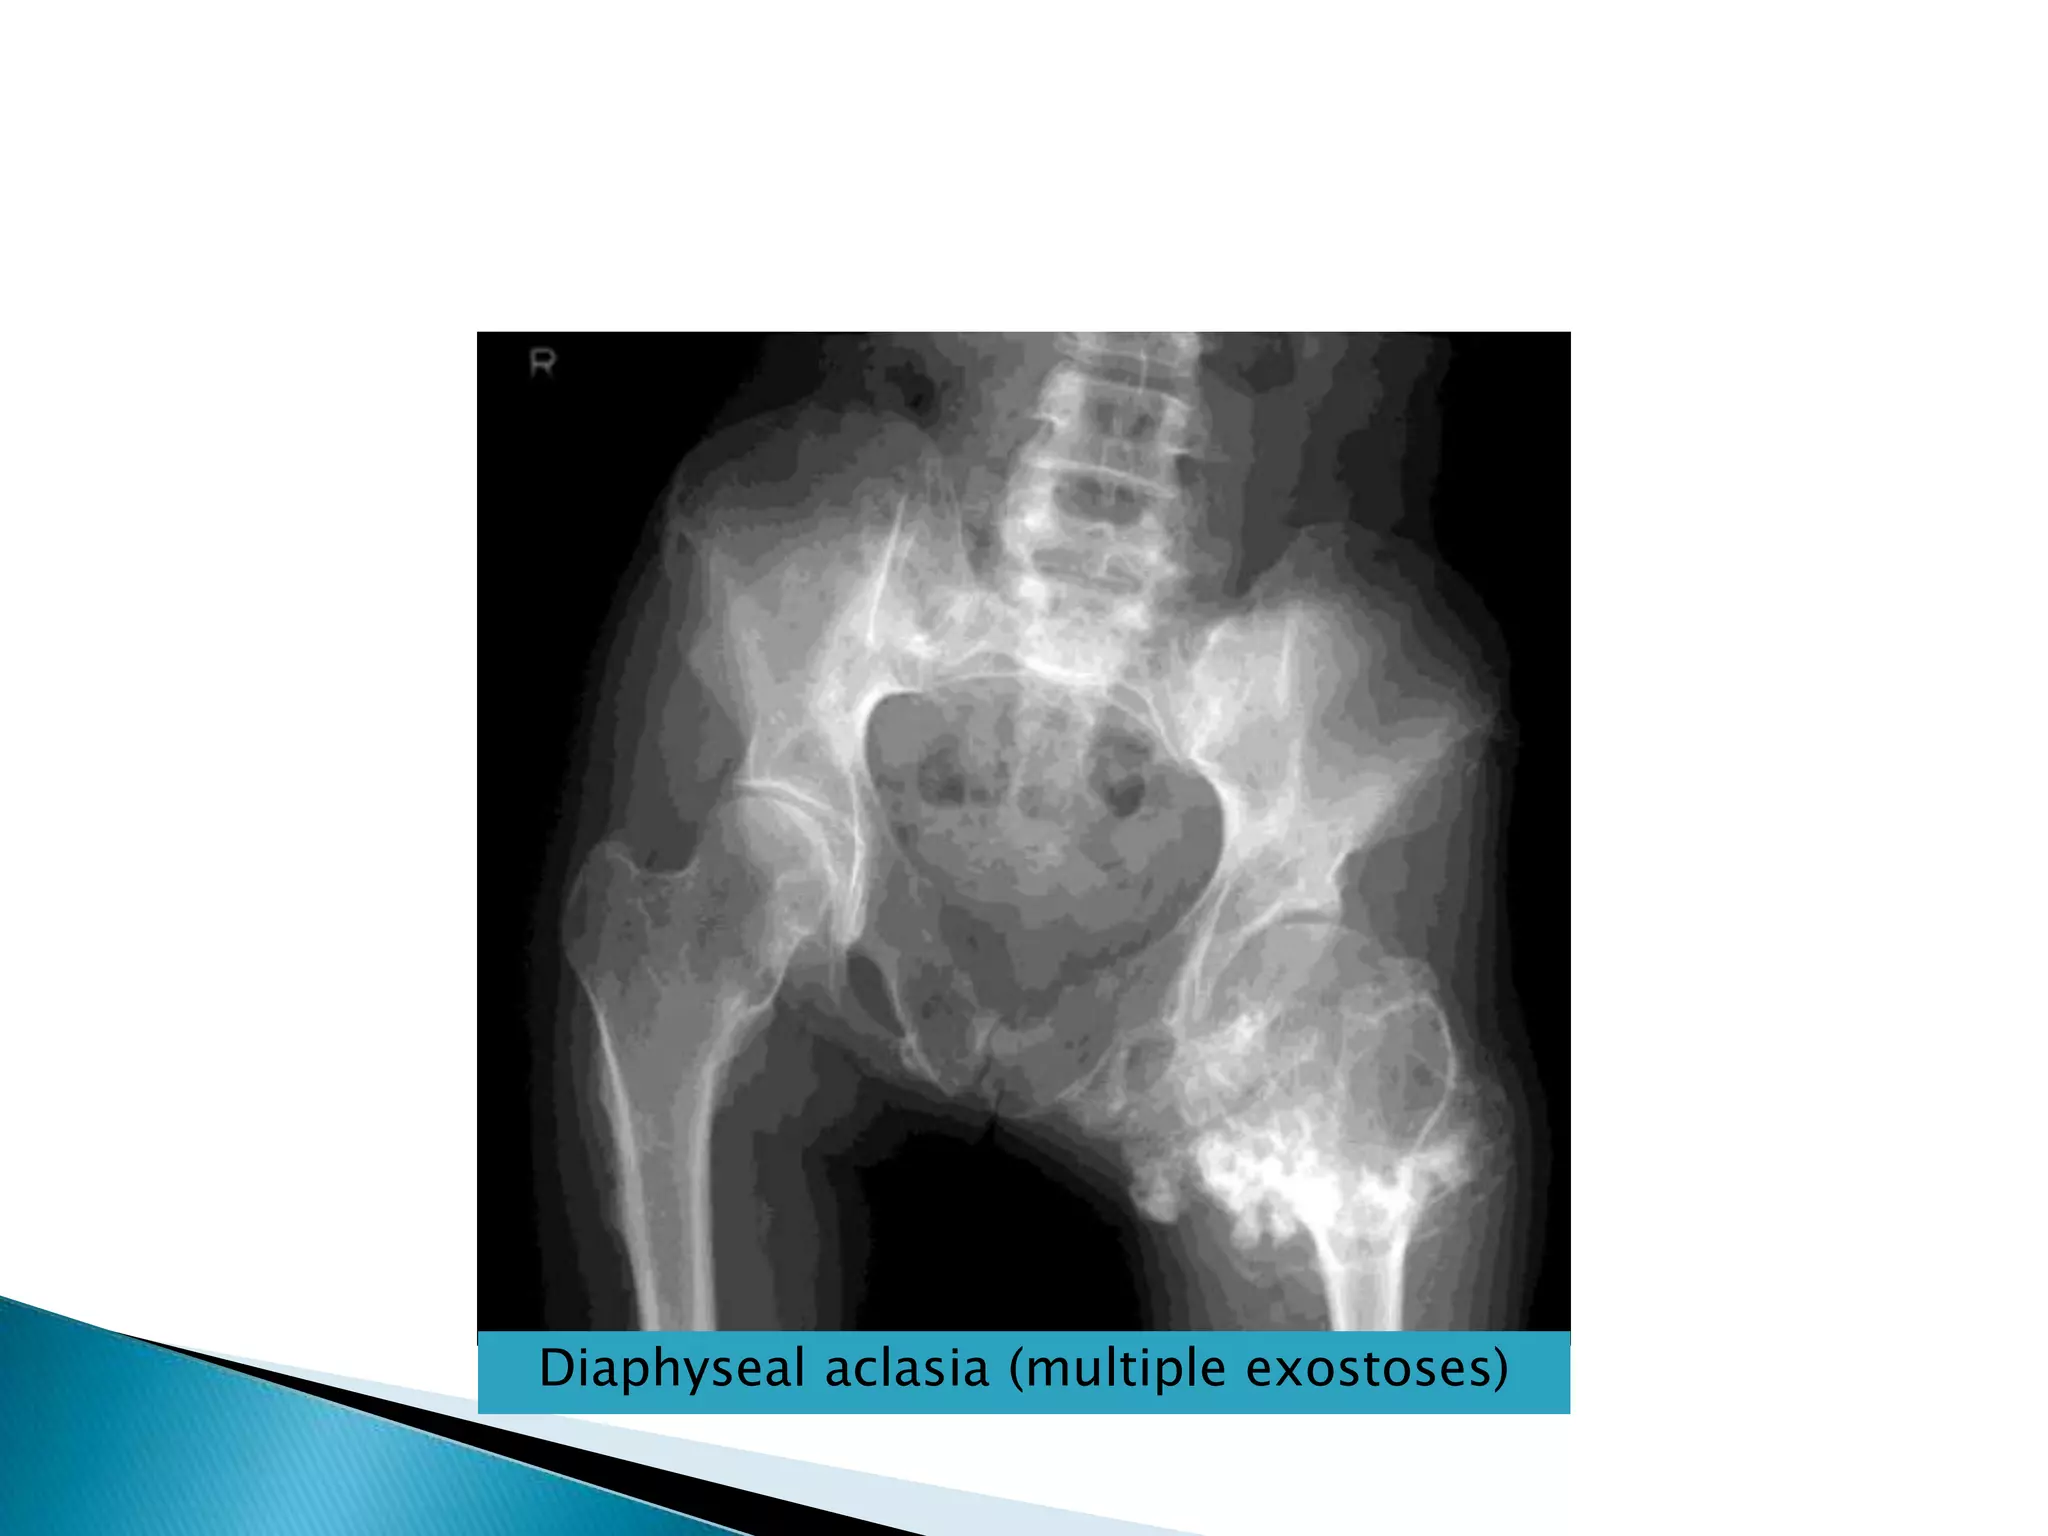

Is congenital disorder.There are multiple bony projections known as osteochondromas or exostoses.They have cartilaginous cup which may contain calcification.When exostoses occur in the long bone , they occur near metaphyses & are directed away form the jointDiaphyseal aclasia (multiple exostoses)

Diaphyseal aclasia (multiple exostoses)